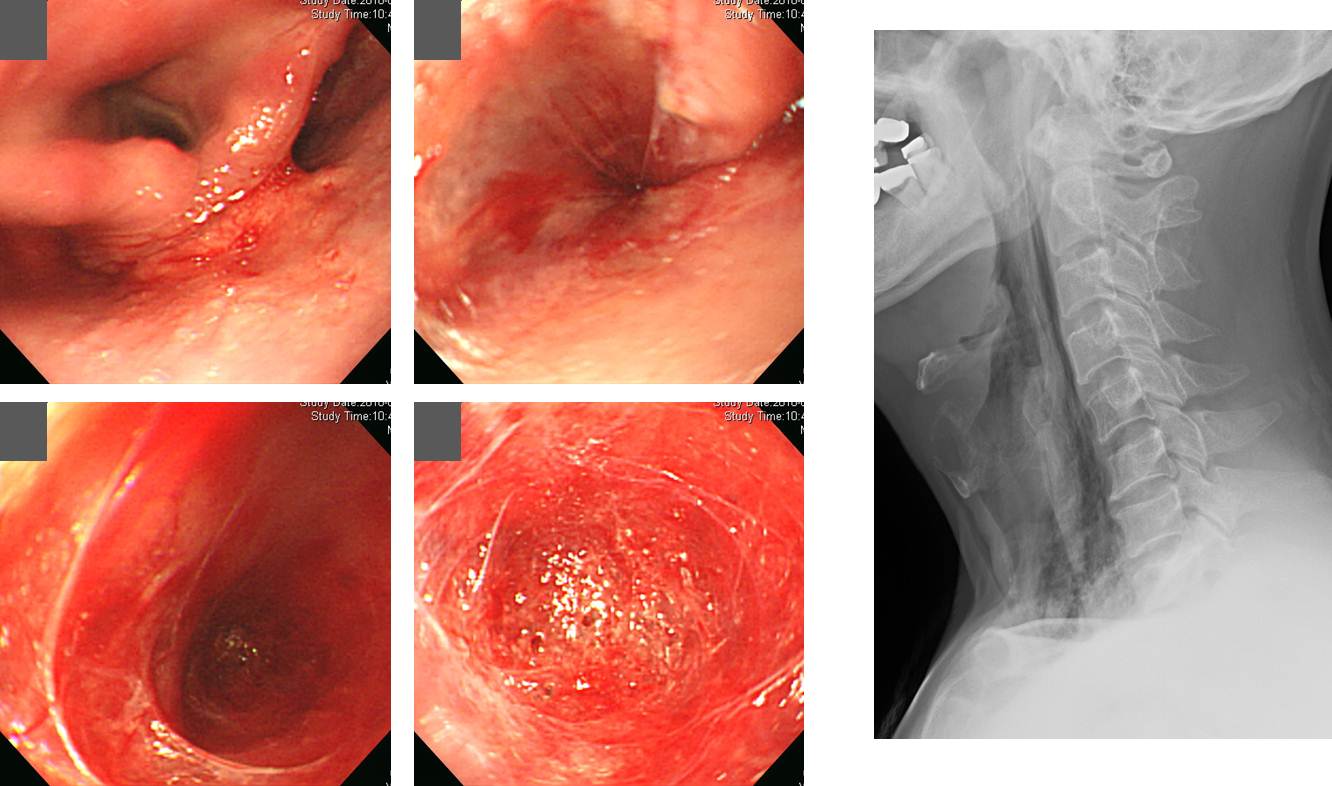

³»½Ã°æ »ðÀÔÀÌ ¾î·Á¿ü´ø ȯÀÚ¿¡¼­ ½Äµµ ±¸¸ÛÀÌ º¸ÀÓ --> õ°ø ÀÇ½É --> Ì¨ãø·Î °á·Ð. »óºÎ½Äµµ °Ô½ÇÀÌ Àִ ȯÀÚ¿¡¼­ ¹«¸®ÇÑ »ðÀÔÀ» ½ÃµµÇϸé õ°øÀÌ ¹ß»ýÇÒ ¼ö ÀÖ½À´Ï´Ù. ÀÌ È¯Àڴ õ°øÀº ¾Æ´Ï¾ú½À´Ï´Ù.

Perforation. ³»½Ã°æ µµÁß °©Àڱ⠽ÉÇÑ ±âħÀÌ ÀÖ¾ú°í, ÀÌ ¶§ scope°¡ ¸¶¿ì½ºÇǽº¿Í ÇÔ²² µÚ·Î ºüÁö¸é¼­ ½Äµµ Áß°£À¸·Î ¹Ð·Á³µ½À´Ï´Ù. ±×·¯¸é¼­ ³»°­ º®ÂÊÀ¸·Î Ÿ°ÝÀÌ °¡ÇØÁö°í, ¿­»óÀÌ ´«À¸·Î È®ÀεǾú½À´Ï´Ù. ÀÌÈÄ ¼Ò·®ÀÇ bleeding°ú ÇÔ²² hematoma°¡ á½À´Ï´Ù. CT¿¡¼­ ¼Ò·®ÀÇ PneumomediastinumÀÌ °üÂûµÇ¾ú½À´Ï´Ù.

Definitive CCRT due to upper esophageal cancer --> deep laceration during EGD --> small amount of free air around the esophagus

Áø´Ü³»½Ã°æ¿¡¼­ ³»½Ã°æÀ» ȸ¼öÇÏ´Â °úÁ¤¿¡¼­ ÀÌ·¯ÇÑ lacerationÀÌ ¹ß°ßµÇ¾î clippingÀ» ¸î °³ ÇÏ¿´½À´Ï´Ù. ´ÙÇེ·´°Ô õ°øÀº ¾Æ´Ï¾ú½À´Ï´Ù.